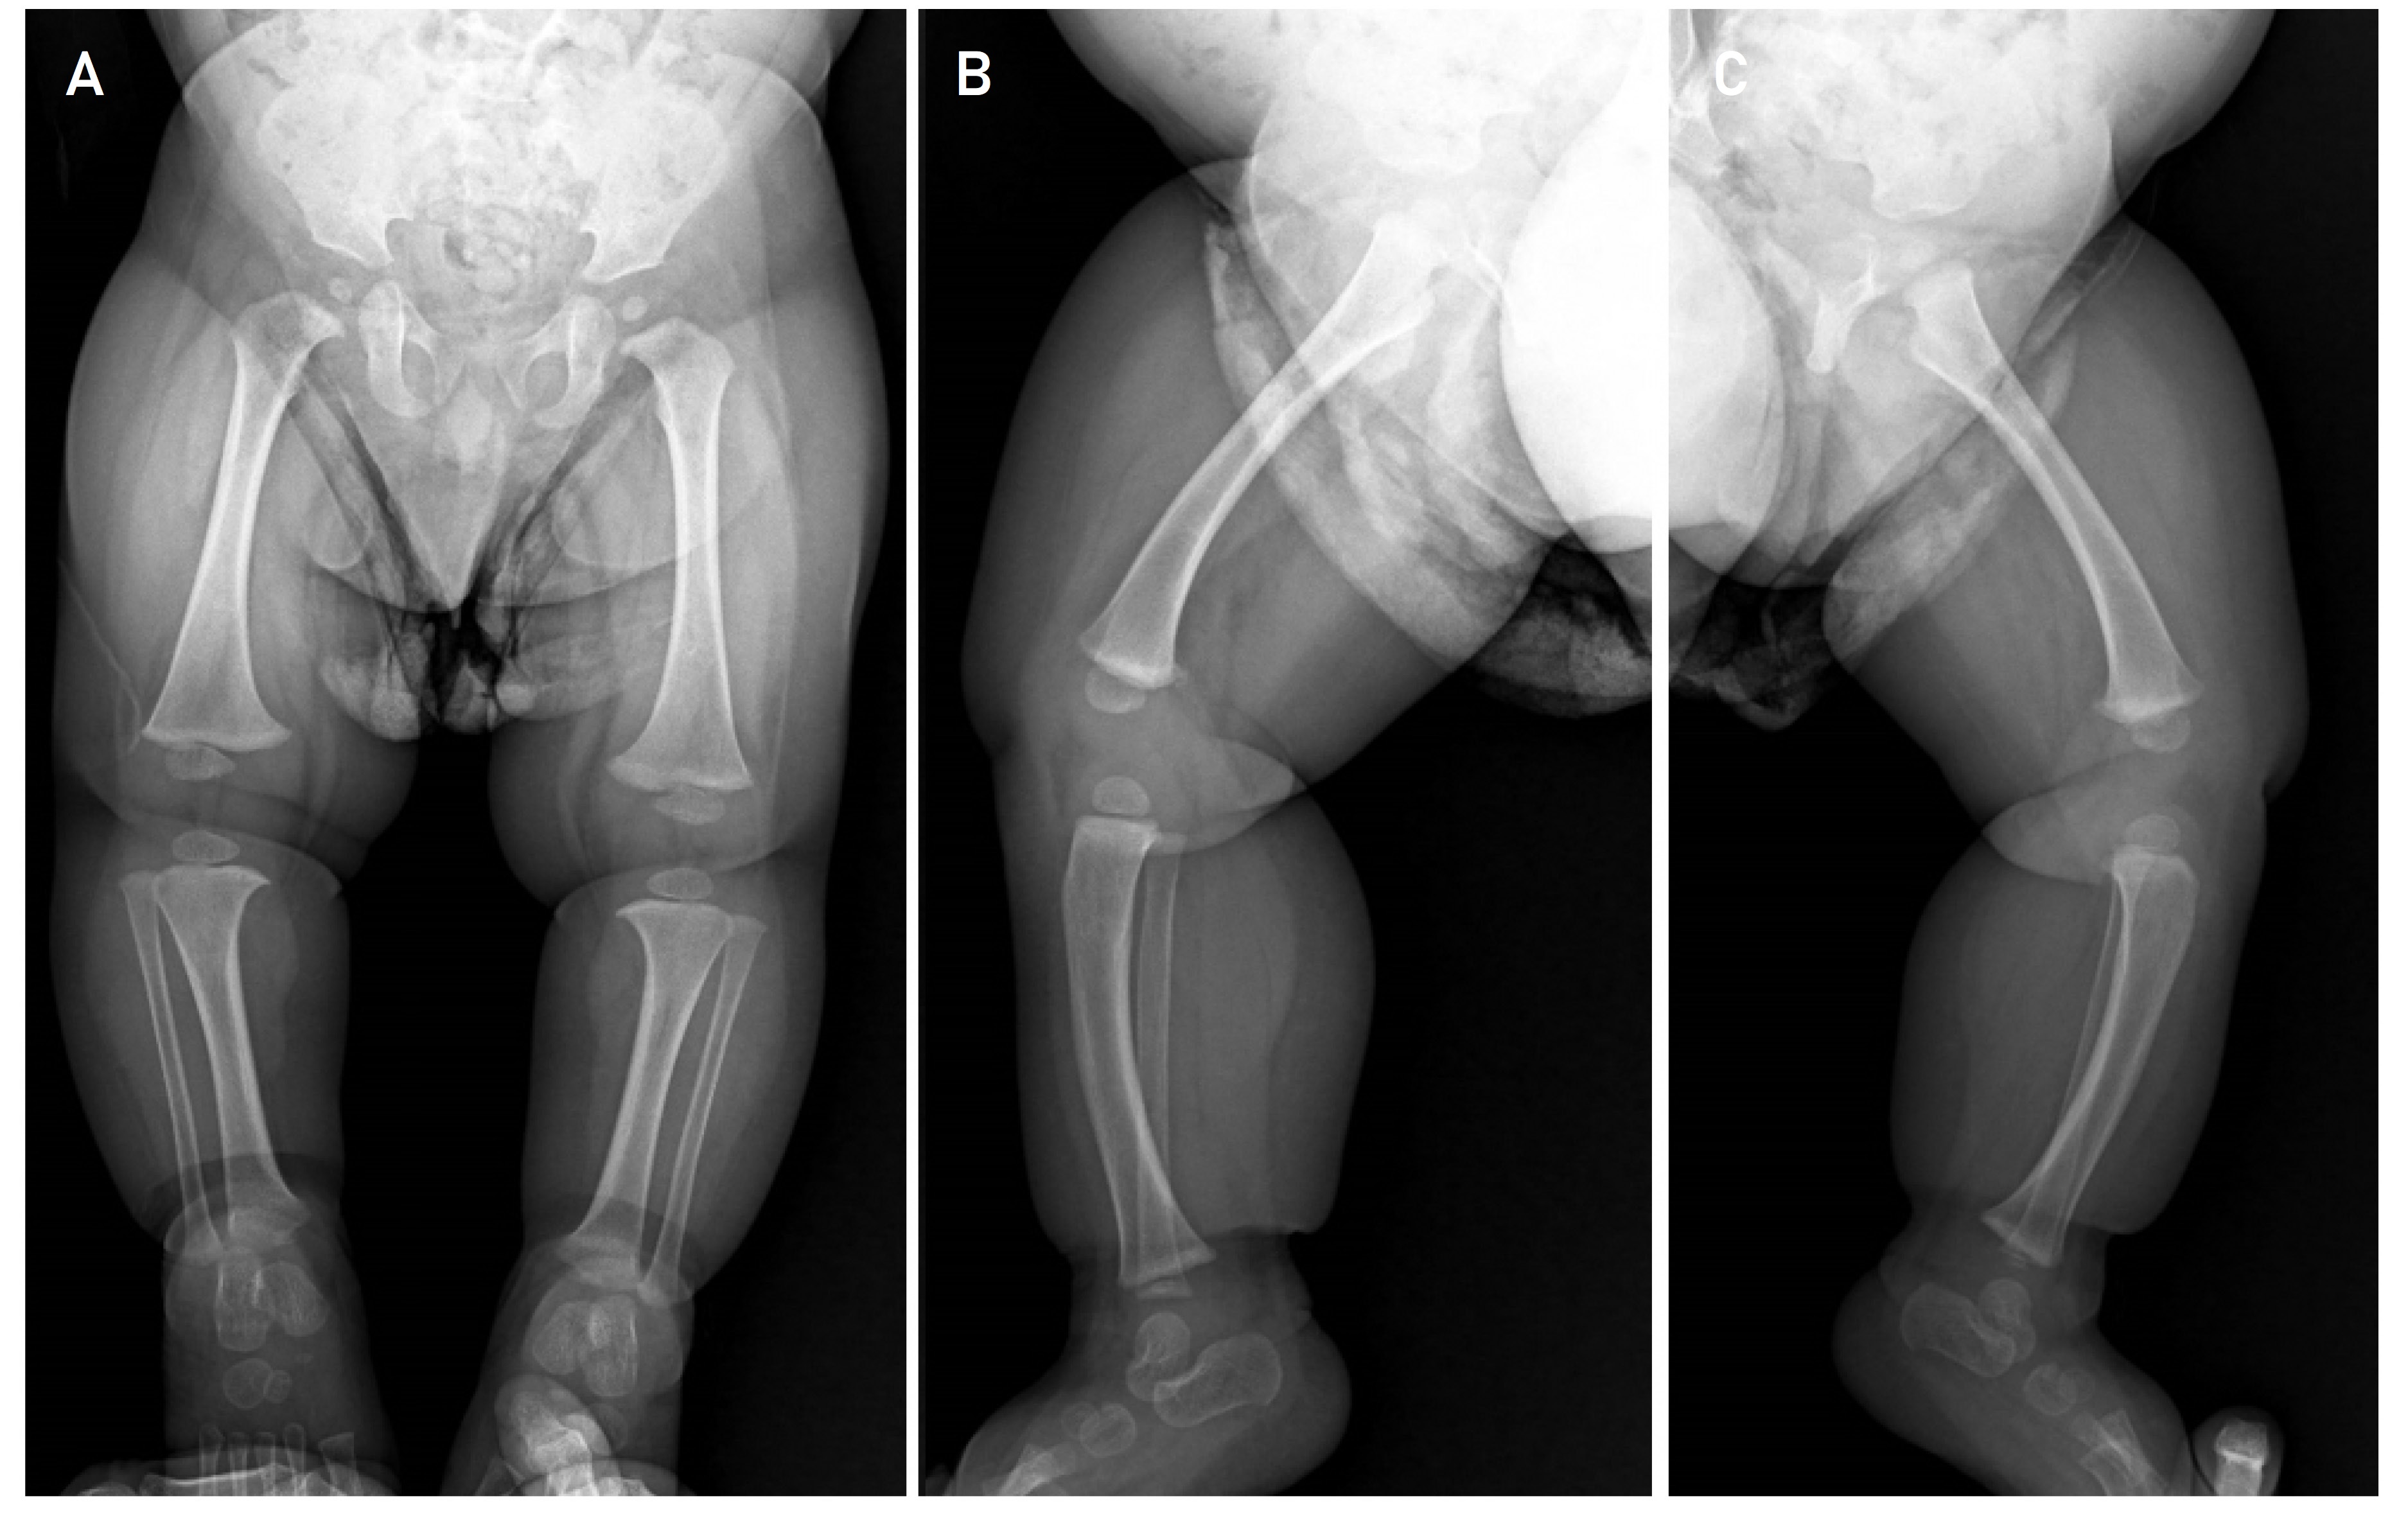

This is a 2-year-old male infant, first child of non-consanguineous parents, with no relevant history of pregnancy and delivery at term and without complications, who is referred to the Genetics consultation by his pediatrician for severe short stature (- 5DS), and with an ongoing diagnostic suspicion process for skeletal dysplasia. The patient has two paternal half-siblings (Figure 1). On physical examination the patient had mild dysmorphologic findings including midface hypoplasia, flat nasal bridge, relative macrocephaly, frontal bossing, brachydactyly and lordosis (Figure 2). Radiographic evaluations at 11 months of the entire skeleton revealed as the only notable finding cup widening of both femurs with discrete longitudinal shortening of both tibias with anteroposterior curvature suggestive of bone dysplasia (Figure 3), and with a bone age study, which revealed an advanced bone age for the age of 1 year and 3 months (4 months). The patient received early stimulation due to the detection of a slight delay in psychomotor development with hypertonia, and at one year of age he was meeting all the developmental milestones. Molecular genetic testing was performed in the evaluation process.

In our case, a probably pathogenic variant (class 2 variant) was detected in the previously undescribed ACAN gene, originating a premature stop codon, which results in a nonsense-mediated-degradation (NMD) of the mRNA of the mutant allele and, therefore, a haploinsufficiency for aggrecan is presumed [14]. The clinical manifestations of our patient, apart from the short stature of - 5 SD, the main cause of consultation and concern, are relatively mild, the most striking features being a slightly prominent forehead and slightly varus lower extremities (Figure 2).